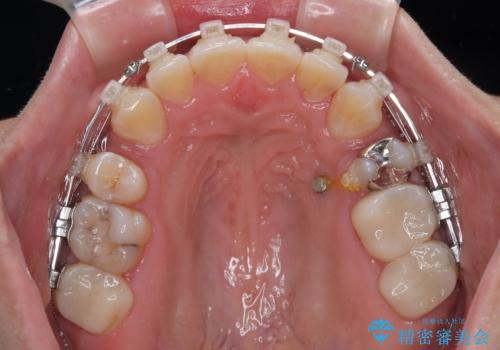

- 矯正装置

- クリアブラケット

- 治療期間

- 2年